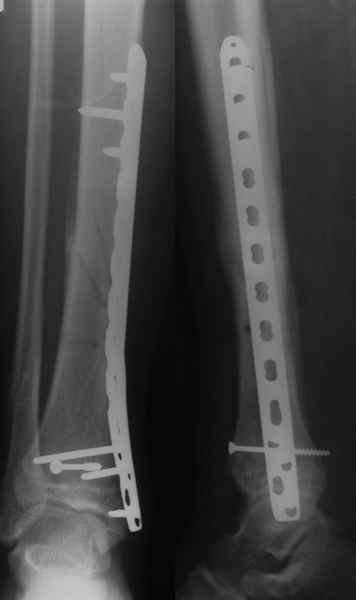

Уважаемые коллеги, остеосинтез малоберцовой кости при переломах пилона помогает решить, как минимум, 3 задачи:

1. шинировать сегмент. При переломах типа С, как правило, остеосинтез большеберцовой кости выполняется по спаданию отёка и заживлению мягких тканей, как и говорит об этом чуть ниже Djoldas. В этот период - с момента поступления пациента в стационар до собственно остеосинтеза перелома пилона мы можем стабилизировать конечность или путём остеосинтеза малоберцовой кости, или ExFix. Естественно, одно не равнозначно другому, для каждого метода есть свои показания в зависимости от характера перелома;

2. за счёт эффекта лигаментотаксиса восстановить правильные взаимоотношения в большеберцово-таранном сочленении. И действительно, я полностью согласен с Вами, Александр, такую же задачу мы решаем зачастую с помощью ExFix. И если наружная фиксация при переломе пилона является не методом первого этапа, а окончательным методом лечения перелома - ни о каком дополнительном остеосинтезе малоберцовой кости, как правило, речи не идёт и идти не должно. Но, если мы решили выполнить внутреннюю фиксацию, желательно помнить, что остеосинтез малоберцовой кости при переломе пилона помогает решить и ещё одну задачу - ортопедическую:

3. стабилизировать наружный опорный комплекс голени и предотвратить вальгусную деформацию голеностопного сустава. Конечно, данная проблема не очень актуальна, или вовсе не актуальна для 43С1, но для повреждений типа 43С2,3, особенно в случаях, когда метафизарный дефект потребовал пластики, а пластину пришлось уложить по медиальной стороне - остеосинтез малоберцовой кости является крайне необходимым - привожу характерный пример.

Но перелом малоберцовой кости может быть и много проксимальнее, и его так же приходится фиксировать из этих же соображений. И особенно, если пациент полный. Из отечественных хирургов на возможность развития такого осложнения - вальгусной деформации голеностопного сустава ч/з 2-3 месяца после операции при переломах типа 43С2 в отсутствии фиксации малоберцовой кости одним из первых указал Виталий Дрягин из ГКБ №3 Челябинска ещё в конце 90х.